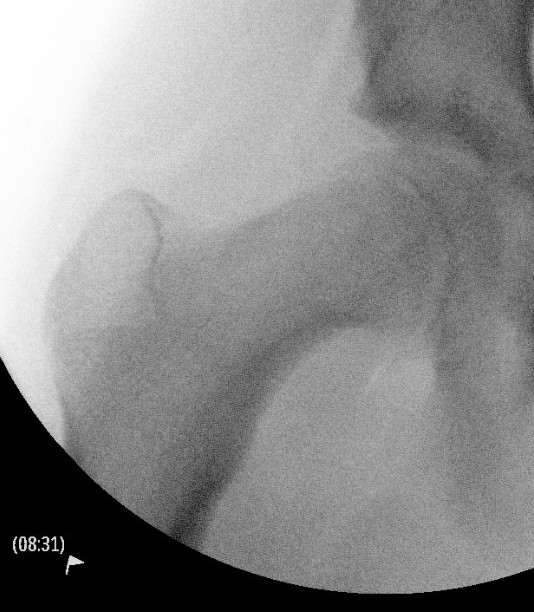

Intra-capsular / Subcapital

Types

Dunn

- trapezoid osteotomy

Fish

- cuneiform